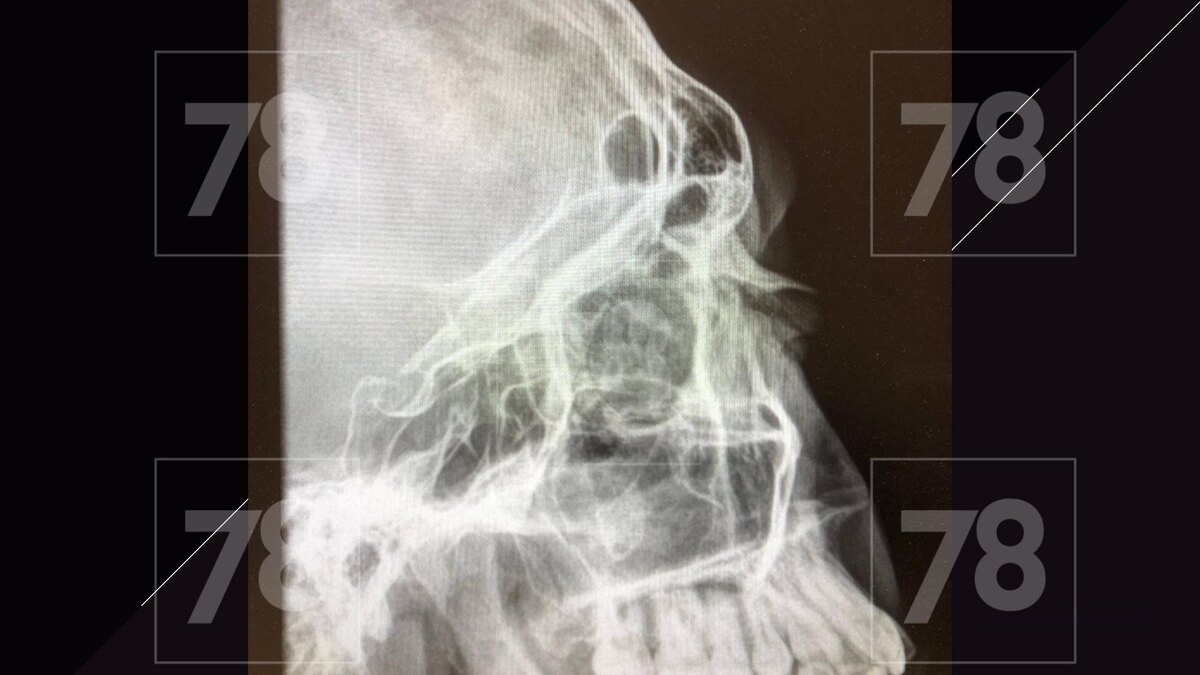

Врачи диагностировали у пострадавшего ЗЧМТ с сотрясением головного мозга, перелом носа со смещением, травматический вывих зуба и многочисленные гематомы.